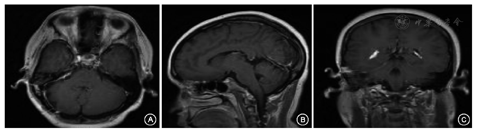

两组患者性别、年龄、既往史(高血压、糖尿病)、肿瘤最大直径以及肿瘤差异无统计学意义(图1)(P>0.05),具体情况详见表1。两组患者中有其他疾病史(手术史,溃疡等病史):监测组4例,非监测组13例,经χ2检验后χ2=3.587,P=0.058,差异无统计学意义(表格中未列出数据)。同时患者术前听神经鞘瘤相关症状比较差异亦无统计学意义(P>0.05),具体情况详见表2。

术中及术后面神经诱发电位及其传导均无明显变化(图2),术后肿瘤完全切除且面听神经走行清晰可见;术中诱发肌电图可见刺激面神经后产生动作电位(图3,图4,图5)。术后3 d两组患者的听力下降后组症状差异无统计学意义(P>0.05);但监测组术后麻木症状发生率显著低于非监测组,面神经功能分级表现也较非监测组有显著提高,差异均有统计学意义(P<0.001);同时发现监测组的面神经功能分级仍然显著优于非监测组(χ2=8.225,P=0.004);而术后1个月监测组其预后GOS评分明显高于非监测组,差异均有统计学意义(P<0.001)(表3)。

所有患者肿瘤均安全切除(图5),监测组出现并发症总人数5例(颅内感染4例:其中1例合并脑脊液漏,吞咽困难1例),非监测组出现并发症总人数10例(单纯颅内感染4例,单纯脑脊液漏2例,颅内感染合并脑脊液漏2例,手术局部渗血2例),经比较,两组术后出现并发症总例数差异无统计学意义(χ2=0.814,P=0.367),脑脊液漏发生率比较,其Fisher精确概率法P=0.691,颅内感染发生率比较,其Fisher精确概率法P=1.000。均未见显著差异。可见手术技术效果无明显差别。